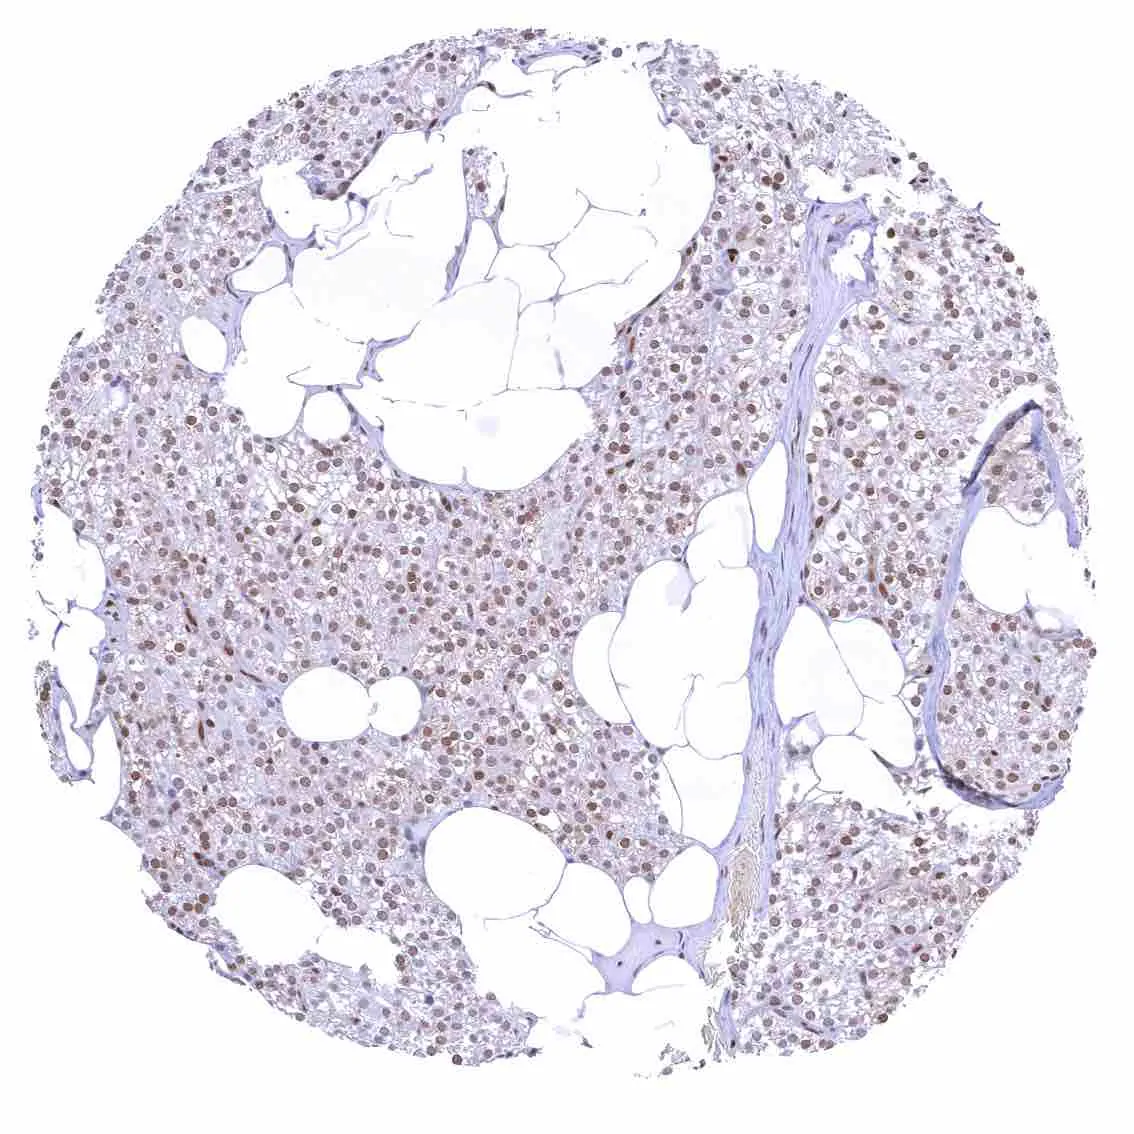

Fat – Variable nuclear p27 staining of at least a fraction of fat cells.